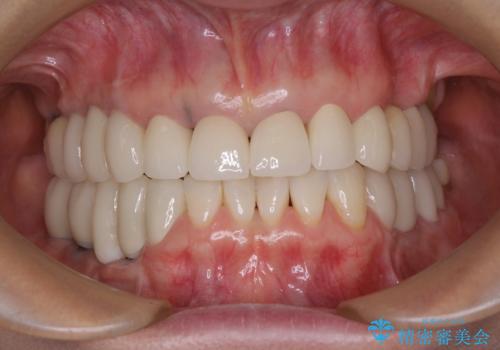

- 前歯のデコボコと奥歯の虫歯を気にして来院された患者様です。

主に下顎歯列全体の後方移動とIPR(歯と歯の間を削る)によってデコボコが解消するように設計し、インビザラインにより治療を行うこととしました。

矯正治療後半に下顎左右奥歯をセラミッククラウンにて補綴し、その後インビザラインによる歯列の仕上げを行うこととしました。

下顎前歯の叢生が速やかに改善されたため、1年3か月で治療を終えることができました。

下顎前歯は後戻りを起こしやすいため、舌側を細いワイヤーで固定することで後戻り対策を行っています。